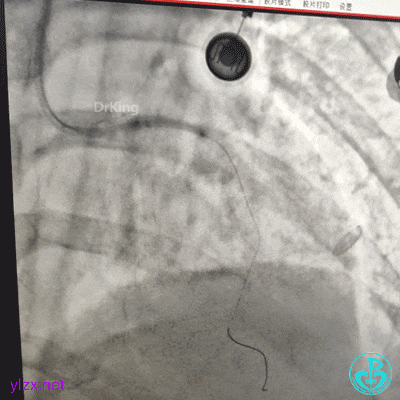

急诊造影

左冠脉造影发现左主干闭塞。

果断更换指引导管。

指引导管刚刚送到升主动脉,患者便发生抽搐、呼之不应,立即胸外按压几次后,患者清醒了,快速置入IABP。造影发现整个前壁不怎么搏动了。